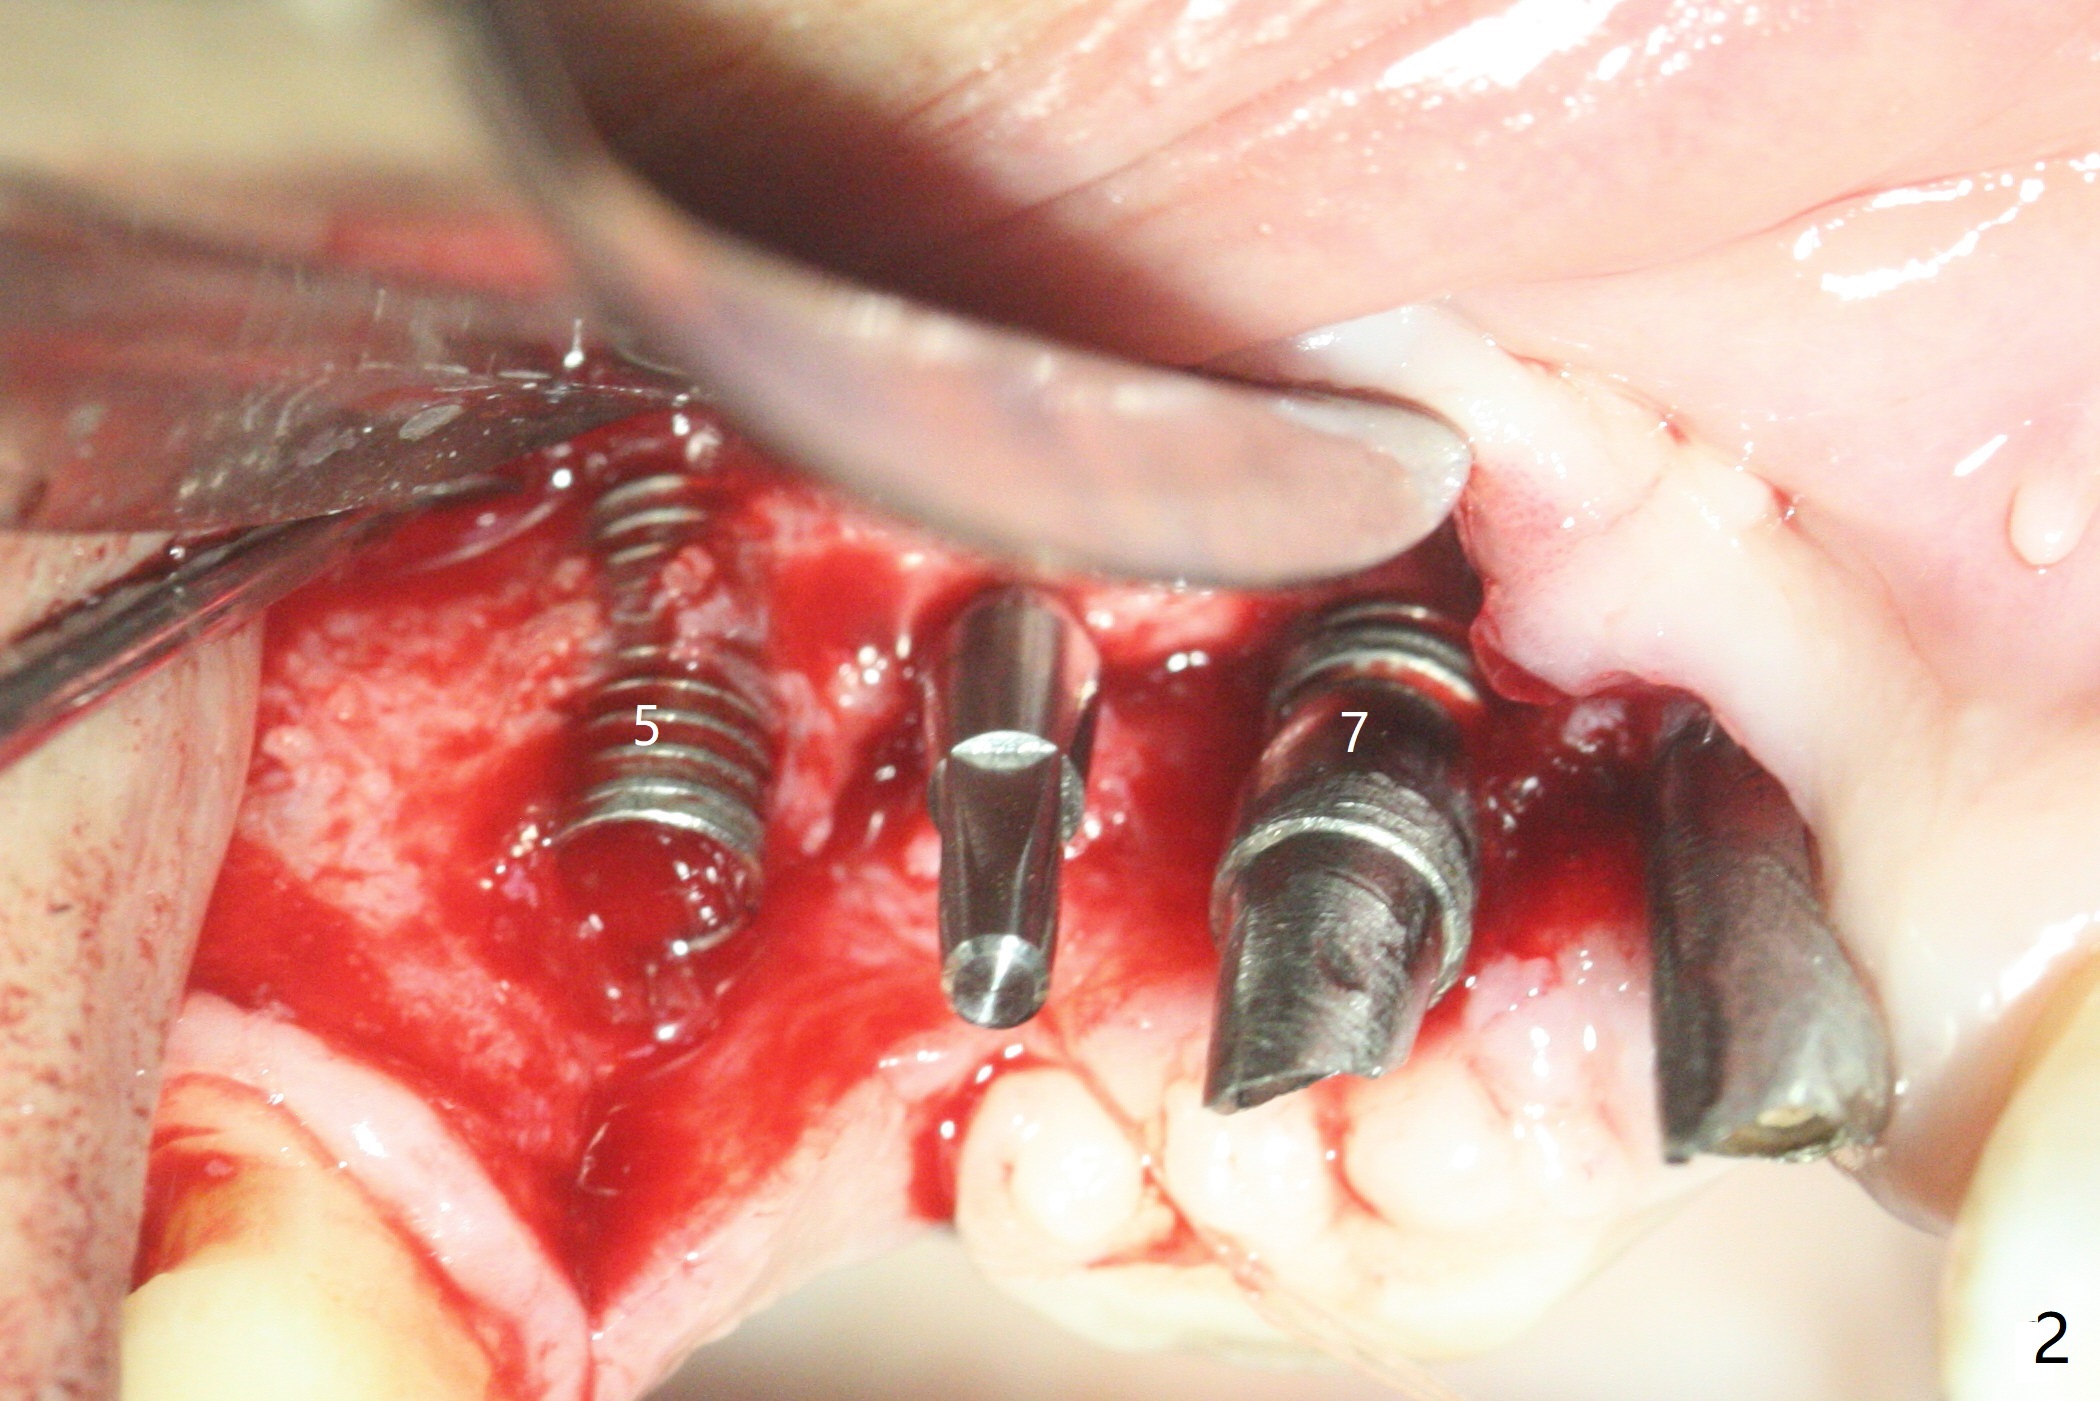

5,7号牙两段式植体种植后螺纹暴露,植骨后4-5个月,准备5号牙uncover,病人主诉7号牙出血,切开后发现两个植体螺纹仍旧暴露(图一,二),看样子保留不住,而6号牙位牙槽嵴不宽,准备植入2x8.5毫米一段式植体,结果骨质高度允许植入10毫米植体(图二,三),然后使用外科钻头和环形刀(trephine bur)取出两段式植体,填入粘性骨粉(图三:*),覆盖PRF和不可吸收膜,4-0 PGA缝合(图四),最后牙周敷料。5,7牙位愈合也可以植入一段式植体,让植体之间距离大些,植骨后颊侧腭侧宽度也可能不足。